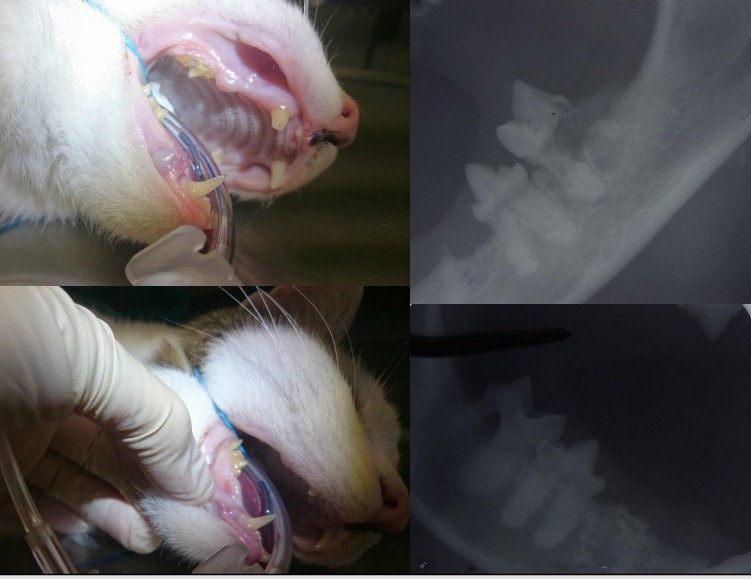

A

stomatitis